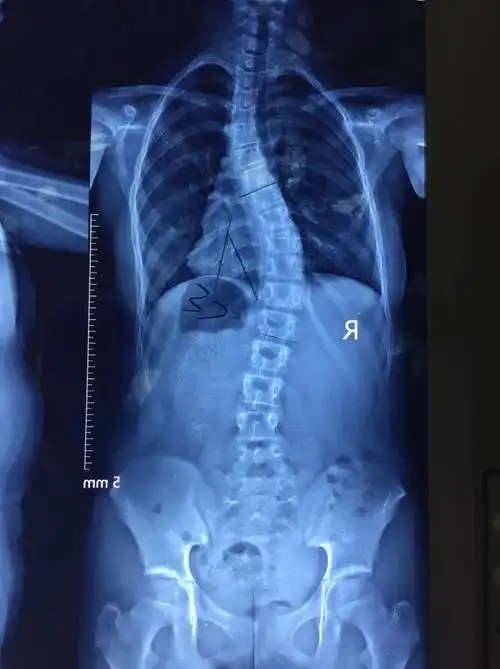

脊柱侧弯最难矫正曲线病例分享

脊柱侧弯超过40度,不一定要做手术05 赵同学979911岁那年,是一

腰椎管狭窄症并脊柱侧弯的治疗前后比较 - 好大夫在线

5岁男童脊柱侧弯超100度心肺功能受影响

体态异常,于是2019年10月份带孩子到外院拍片检查,确诊脊柱侧弯已经